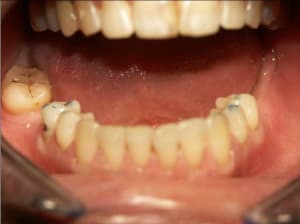

genb_kzx0m9.jpg

Voir le message contenant cette image